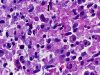

Panel A to E are intra-operative cytologic preparation, Panel E to J are frozen section, Panel K to N are permanent sections, Panel O to T are immunohistochemistry.

The clinical history of this case is very interesting and also complicated. The same is true for the intra-operative consultation. At low magnification of the cytologic preparation, there are clusters of cells that are suggestive of glial cells (Panel A). On high magnification, many of these cells have loose, pale granular to foamy cytoplasm and some of these cells have enlarge nuclei (Panel B). Interestingly, these cells admixed with substantial number of foamy cells most consistent with foamy histiocytes (Panel C, D, and E). Mitosis can be occasionally seen (Panel D). On the frozen section, the biopsy material is extensively necrotic (Panel F). In the small amount of viable tissue available for examination (Panel G), there is one focus suggestive of endothelial proliferation (Panel H). The cells are similar to those seen in the cytologic preparation which is a mixture of foamy cells suggestive of histiocytes and some cells with atypical nuclei (Panel I and J)

Permanent Sections:

Findings in the permanent sections are not that much different from that of the frozen section cytologic preparation. In essence, the lesion is composed predominantly of moderately sized found to oval cells with foamy cytoplasm morphologically consistent of histiocytes and the level of nuclear pleomorphism is not particularly distinctive (Panel K). With diligent search, there are cells that have foamy histiocytes but with rather atypical nuclei (arrow in Panel L). In some areas, the level of nuclear pleomorphism is really low and the foamy cells are indistinguishable from histiocytes (Panel M and N). On immunohistochemistry for CD163, a marker for histiocytes, many but not all of the foamy cells are positive (Panel O and P). In particular, cells with enalrged nuclei with or without prominent nucleoli are negative (arrows in Panel P). Comparatively, the positive cells have small nuclei compatible with histiocytes. In some areas that are composed cells predominantly that gives the morphology of histiocytes, many of the cells have a granular cytoplasmic positive reactivity for glial fibrillary acidic protein (GFAP) (arrow head in Panel Q) but some of these cells have solid cytoplasmic positive staining. (arrow in Panel Q). In other areas where cells with enlarged and atypical nuclei are found, the cells has solid positive cytoplasmic staining (Panel R). The cells with enlarged nuclei are often positive for p53 (Panel S) and many cells with enlarged nuclei are positive for Ki67 (Panel T).